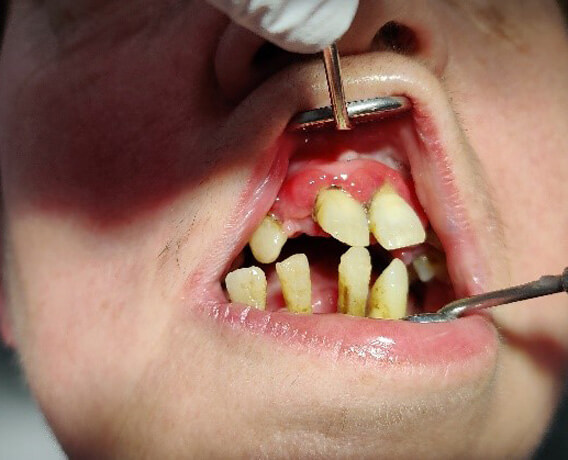

Biss nach PZR

Entzündungen und Rezessionen sind deutlich erkennbar.